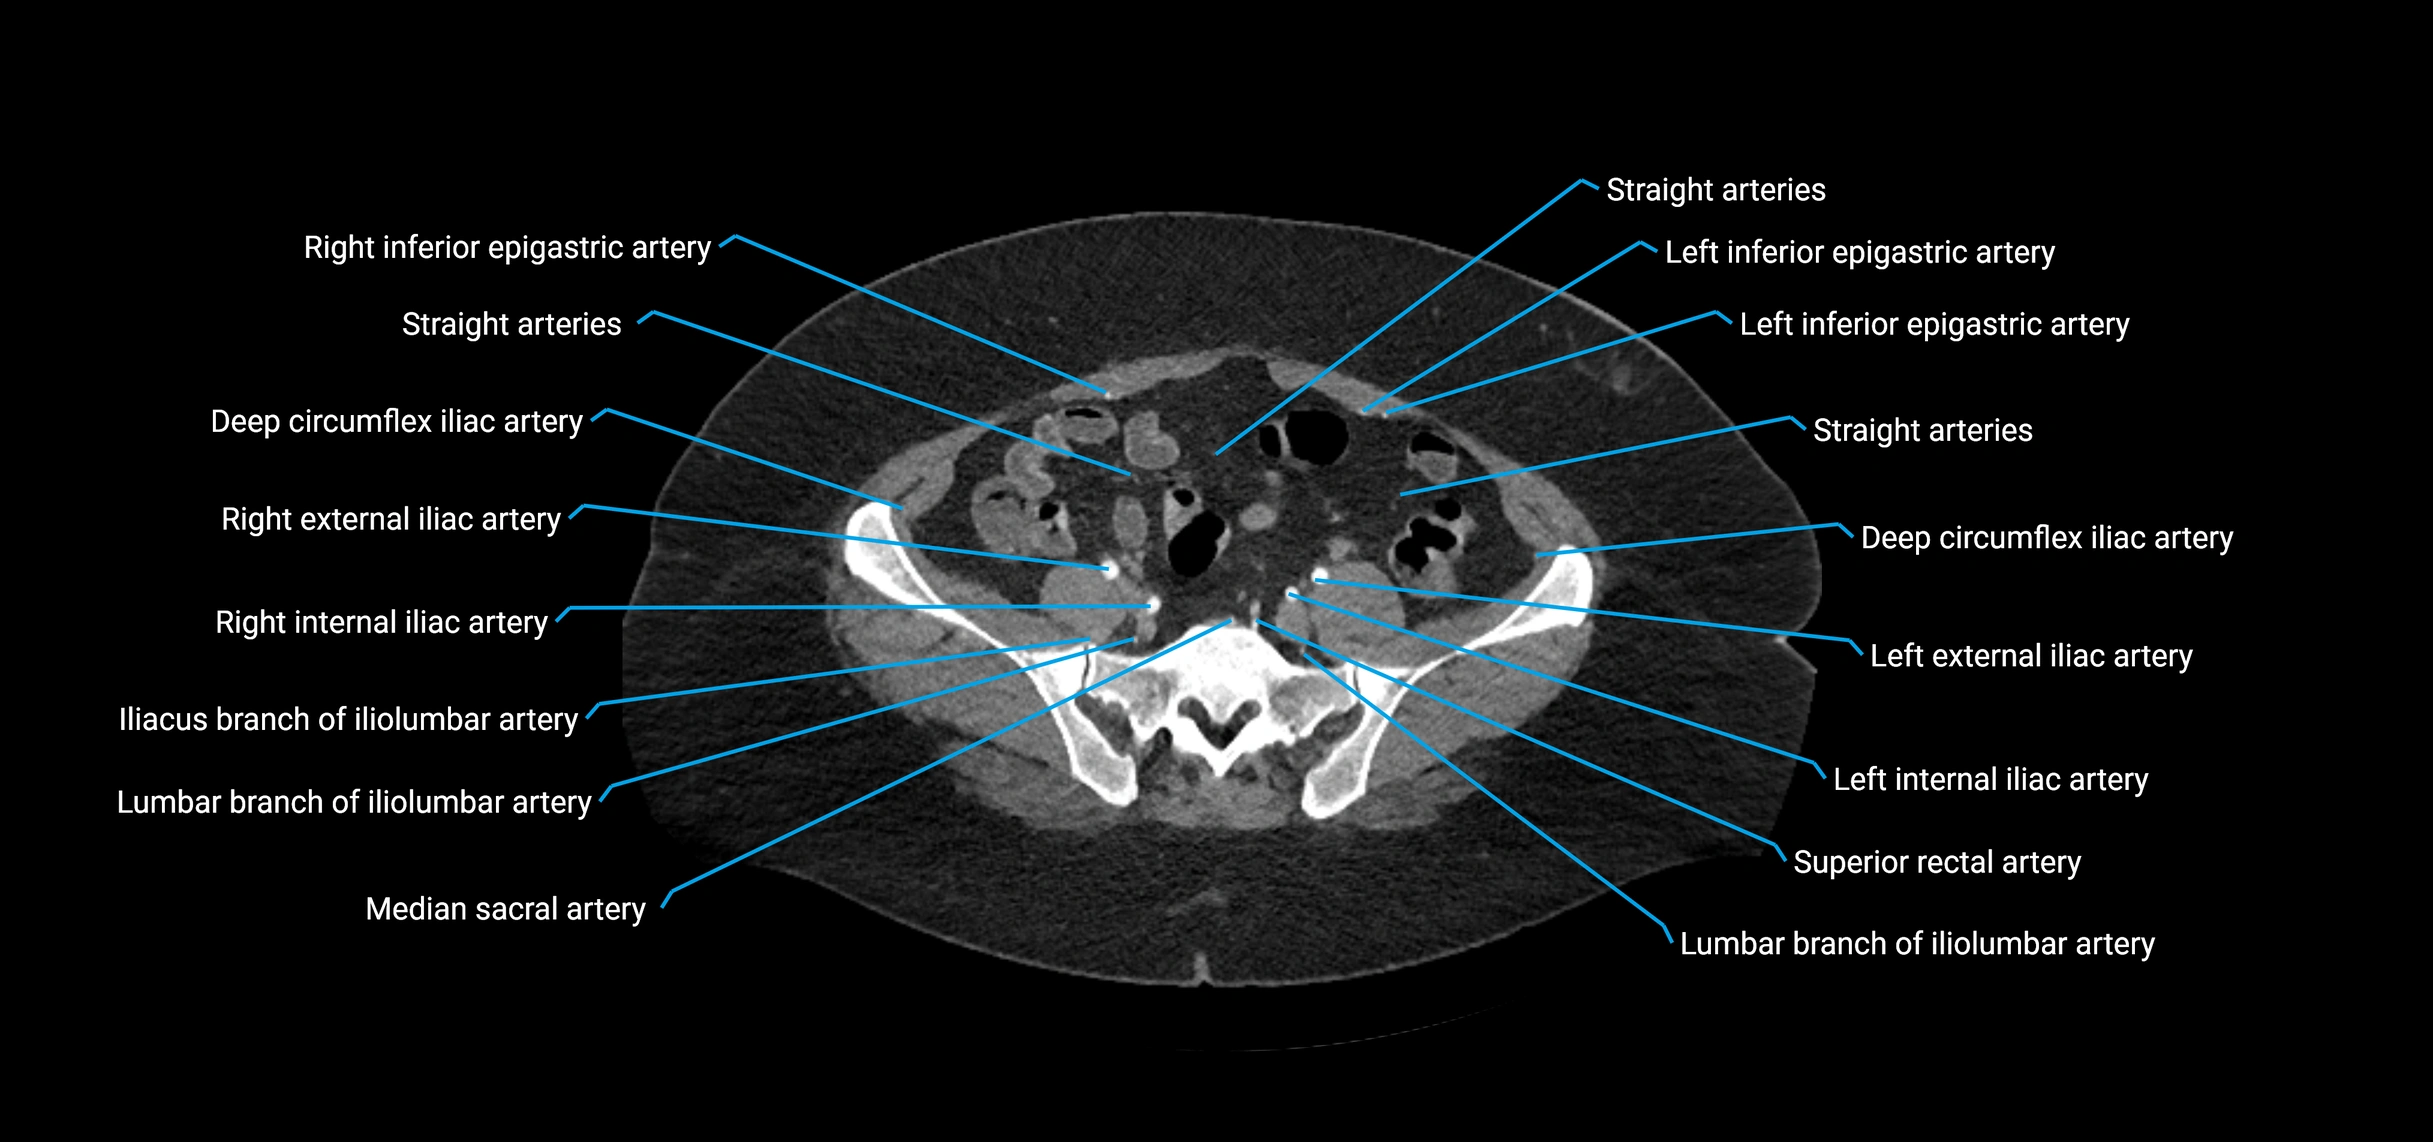

Contrast-enhanced CT (CTA):

• Gold standard for abdominal aortic imaging

• Provides excellent detail of lumen, wall, aneurysm, thrombus, and branch vessels

• Multiplanar and 3D reconstructions help in aneurysm measurement, stent graft planning, and dissection evaluation

• Detects acute rupture, traumatic injury, or occlusion with high sensitivity